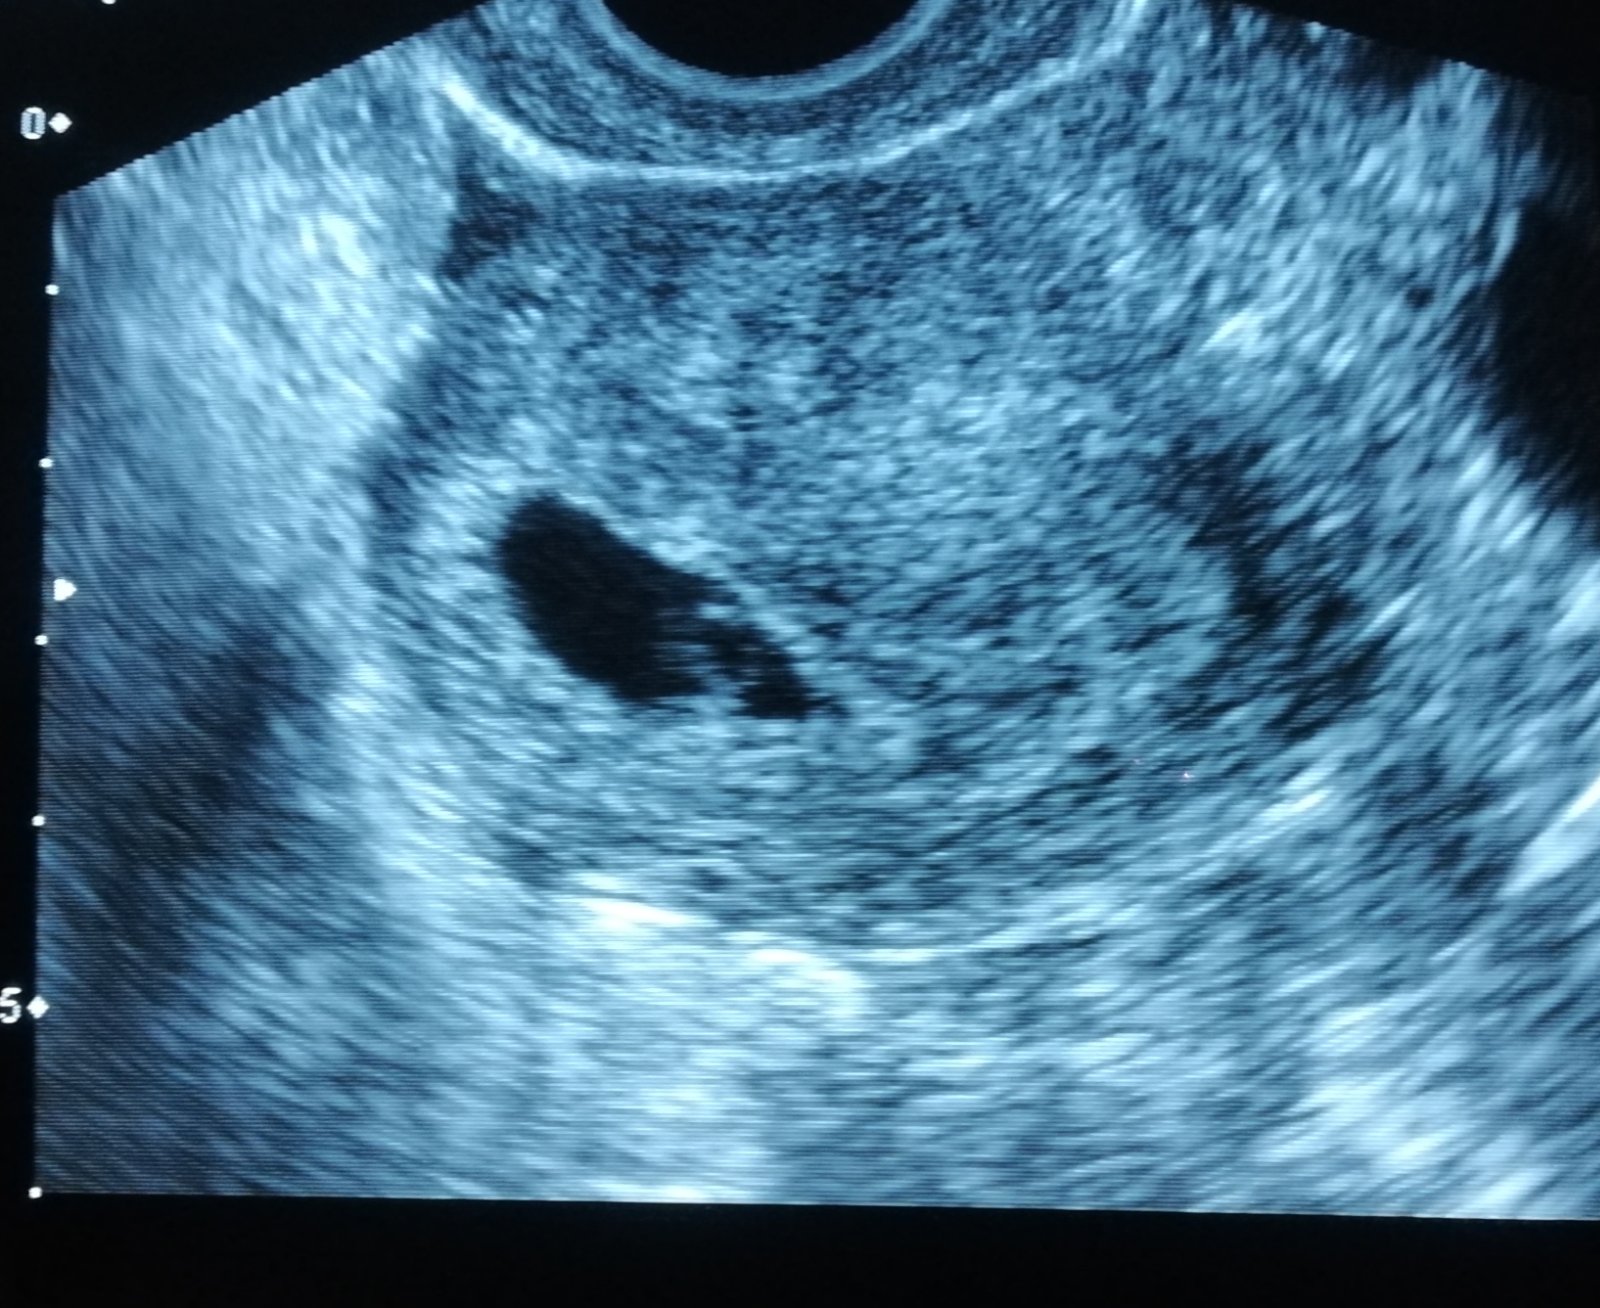

Jinak u nas vse v poradku, dneska jsem byla na UTZ a byl tam budouci mimisek <3 ale je to vse stres, aby vse bylo jak ma